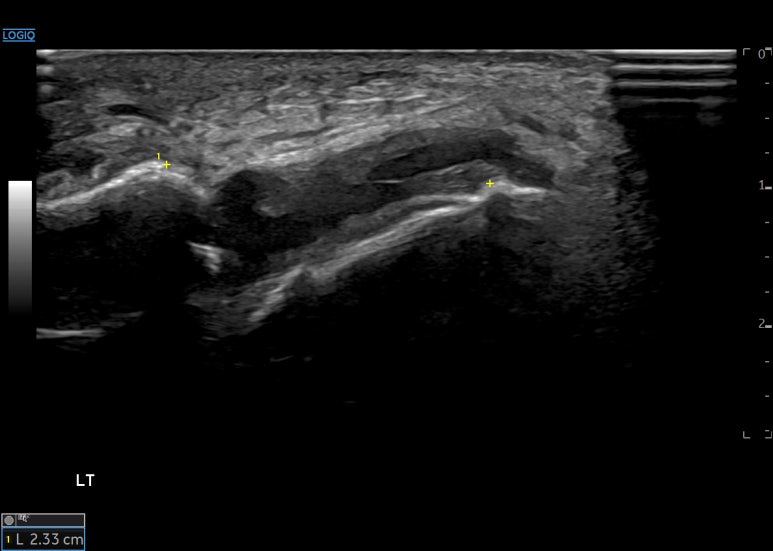

안정시에

두 뼈 거리는

1.92cm 였고요.

내번 스트레칭할 때

두 뼈 거리는 2.33cm로

4.1mm 벌어집니다.